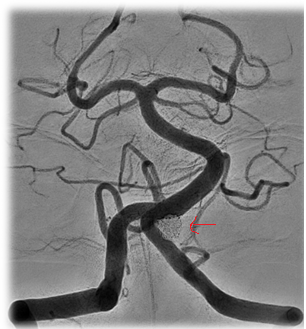

![]() Figure 3: Final angiographic result. Note the red arrows showing the final coil mass. |